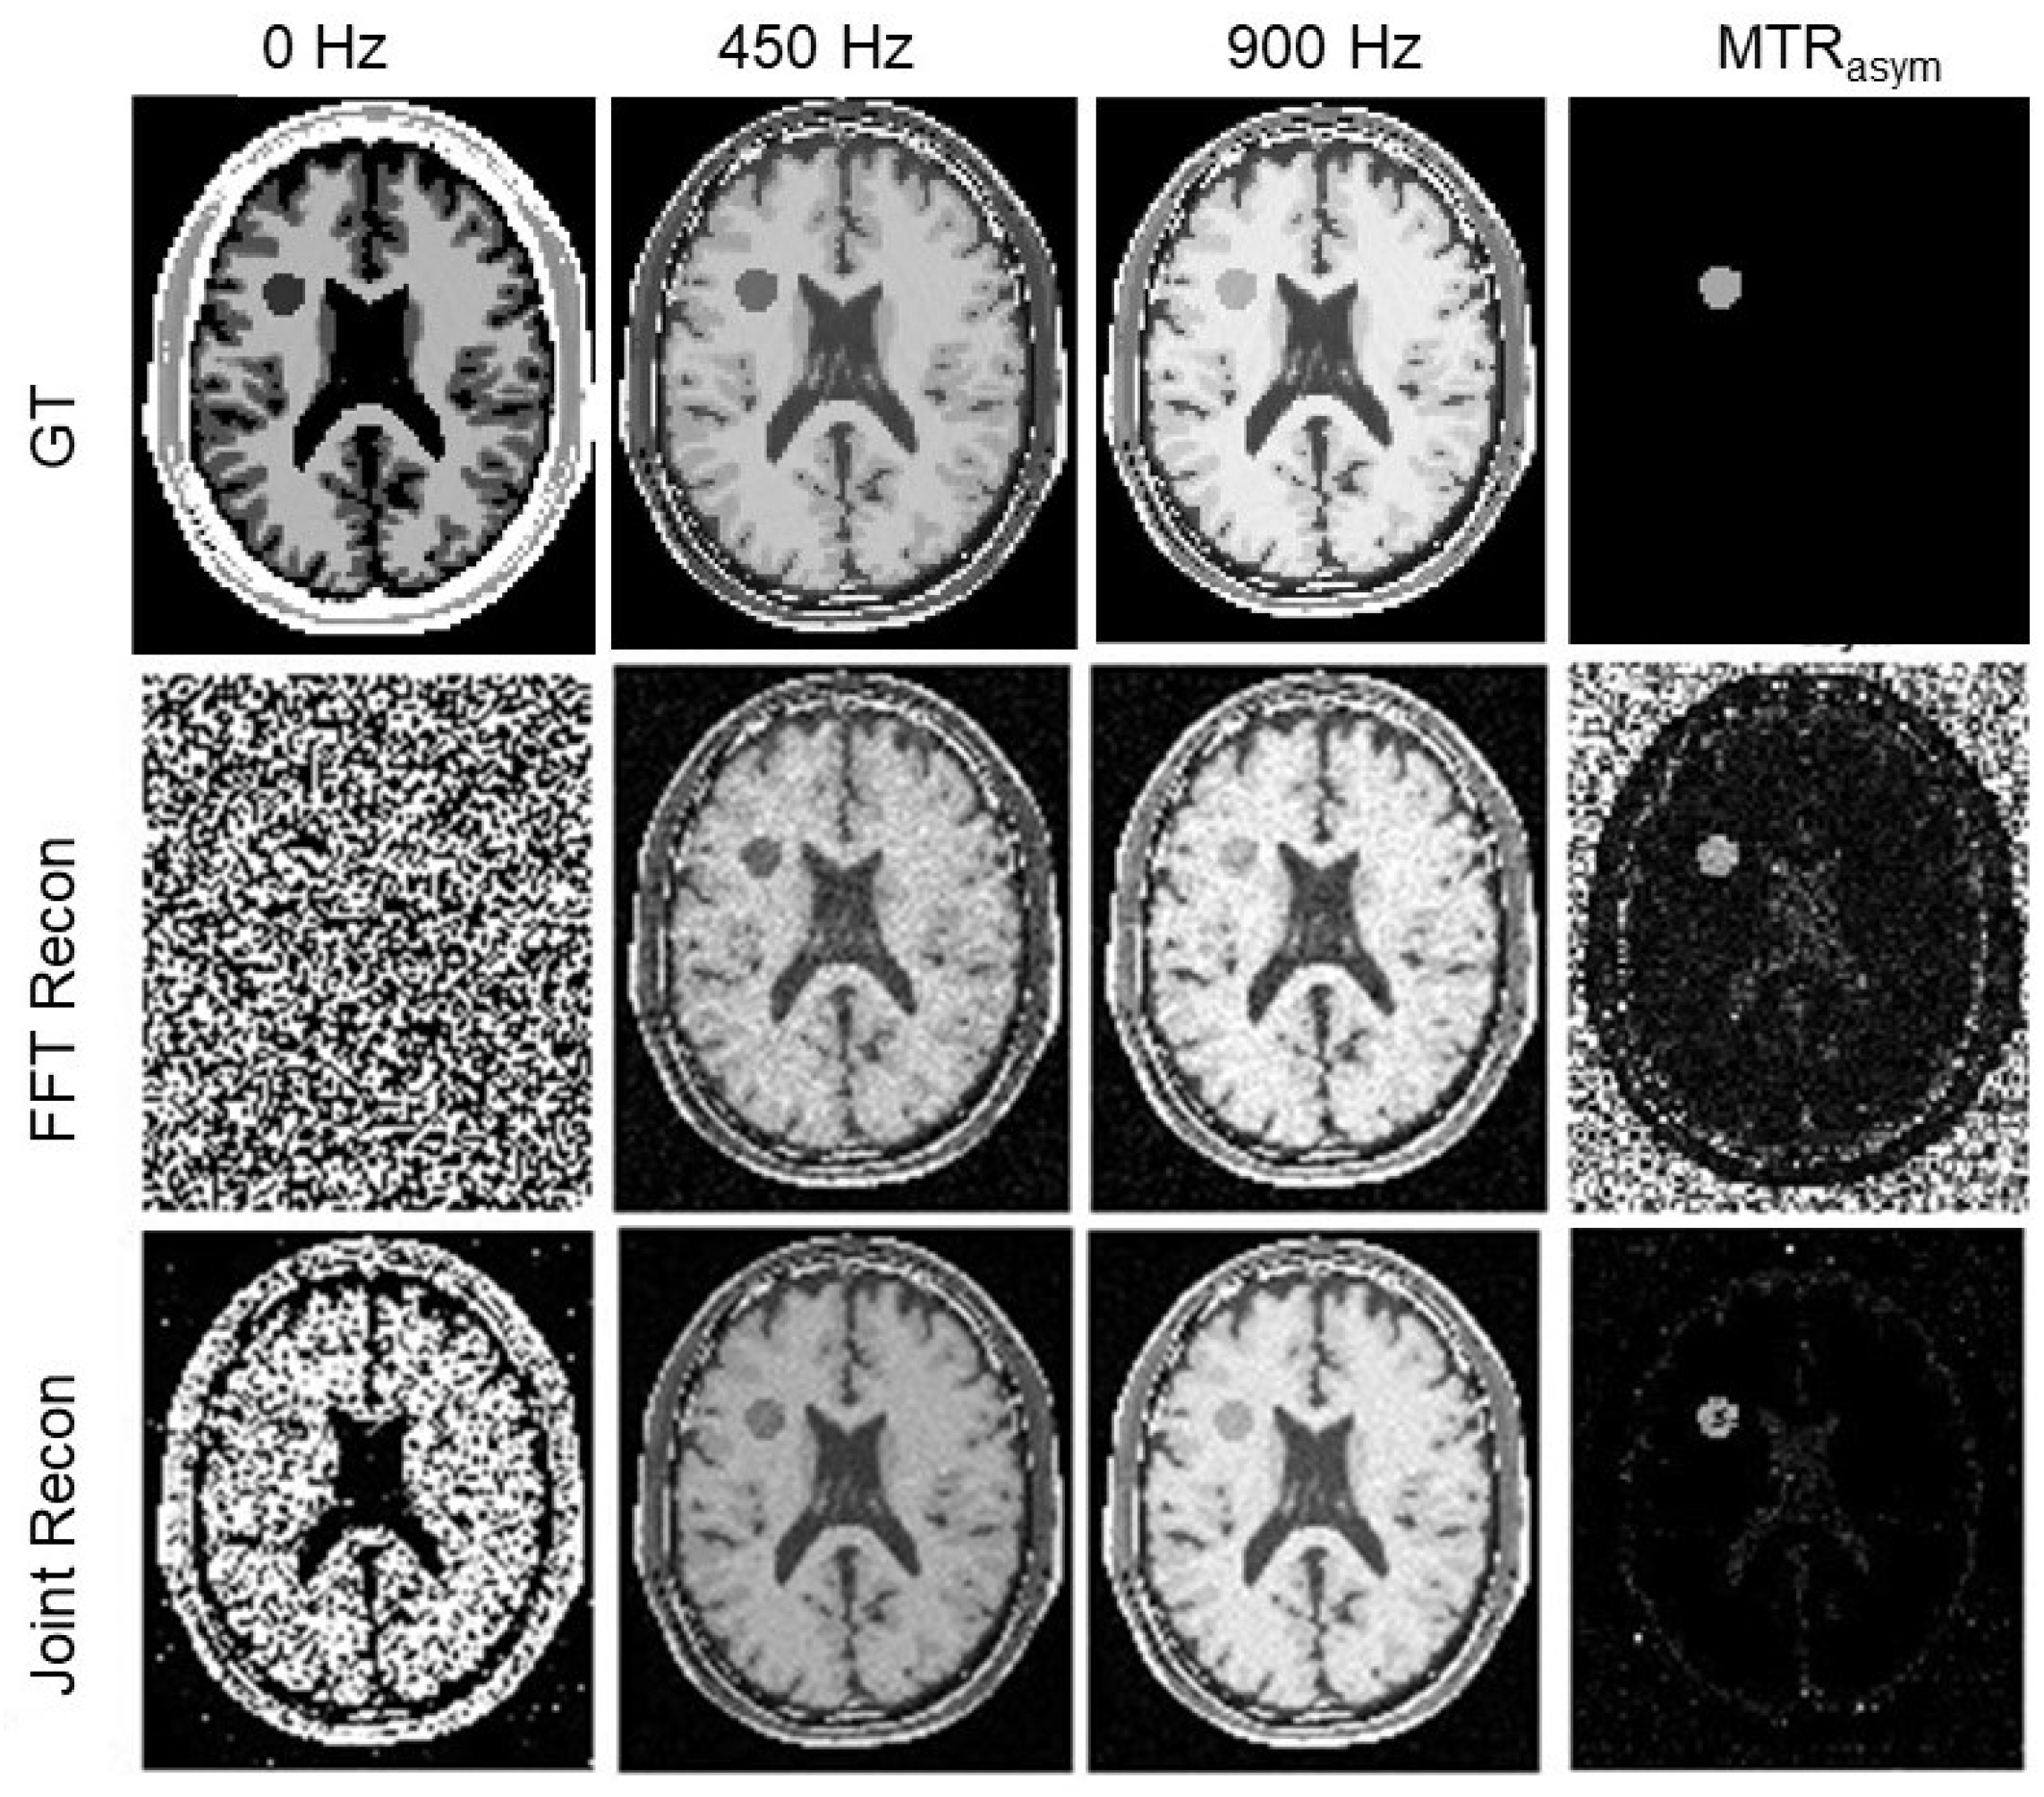

3.3. Results of Choline Phantom Case